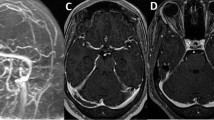

The role and timing of repeat neuroimaging in assessing recanalization and thrombus burden is unclear. The recent prospective PRIORITy-CVT study, which imaged 68 individuals with CVT with standardized MRI/MR venography at 48 h, 8 days and 90 days following initiation of anticoagulation, found that 74% had partial (68%) or full (6%) recanalization within 8 days of initiating therapy, and 95% had partial (41%) or complete (54%) recanalization by 90 days [73••]. While early recanalization was associated with regression of non-haemorrhagic lesions, there was no association between recanalization status and new or enlarged haemorrhagic lesions, or recanalization status and favourable functional outcome.

There is inconsistent evidence for whether recanalization is associated with functional outcome, and what the directionality and time-dependence of that relationship may be. Neither PRIORITy-CVT [73••] nor a prospective substudy of RESPECT-CVT found an association between recanalization and functional outcome [74]; however, both were likely unpowered for this outcome. A recent meta-analysis examining the association between recanalization and prognosis found that complete or partial recanalization was associated with an increased odds of functional independence (mRS 0–1) [75]. However, all 19 studies included were appraised as having moderate or low methodological quality, and definitions of recanalization and timing of clinical and imaging assessments were variable between studies. The significance and prognostic implications of recanalization status are yet to be fully determined.

In PRIORITy-CVT, residual headache was not associated with recanalization status. A large prospective series of 325 individuals with CVT from China described an association between severe headache (residual headache requiring bed rest or readmission to hospital 1 month or less prior to follow-up assessment, with a median time to follow-up of 13 months) and absence of recanalization, though follow-up neuroimaging was not systematic [76].